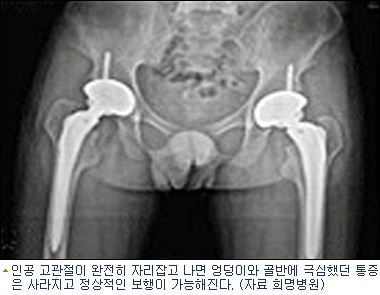

인공 고관절이 완전히 자리잡고 나면 엉덩이와 골반에 극심했던 통증은 사라지고 정상적인 보행이 가능해진다.

하지만 인공관절수술은 정밀 검사를 통해 고관절의 크기와 각도를 정확히 측정해야 하고 수술과 재활치료에 대한 환자 본인의 충분한 이해와 의지가 필수다. 또한 수술 후에는 정기적인 검진을 통해 관절의 상태를 점검 받아야 한다.